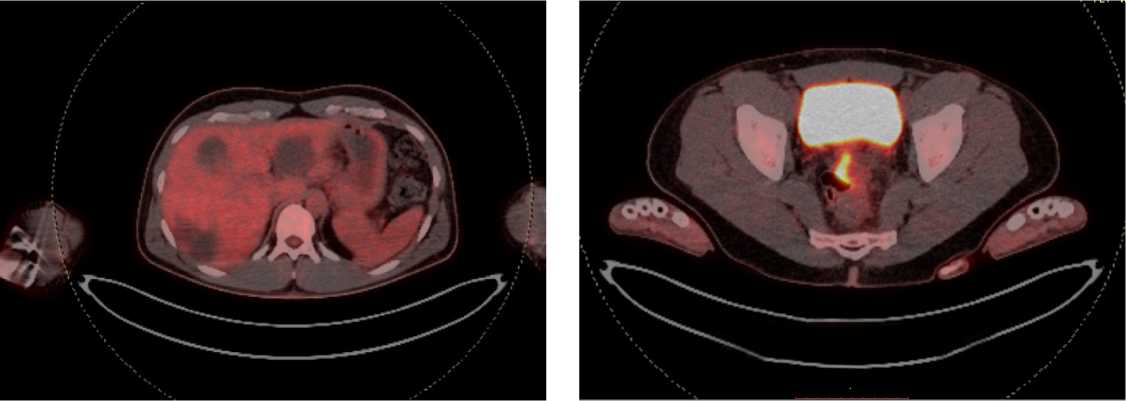

По решению онкологического консилиума пациенту начат ПХТ 1 линии в режиме FOLFOX + бевацизумаб. С 02.09.2022 проведено 3 цикла ПХТ 1 линии, по результатам контрольных обследований зарегистрировано прогрессирование процесса за счет роста образований печени до 64 × 46 мм и появления линзовидного образования между передней поверхностью прямой кишки и задней поверхностью предстательной железы размерами 47 × 15 × 25 мм (рис. 7, 8).

Рис. 7. Результаты компьютерной томографии органов брюшной полости у пациента 37 лет с диагнозом метастатический колоректальный рак с признаками микросателлитной нестабильности (октябрь 2022 г., после 3-х циклов FOLFOX + бевацизумаб)

Fig. 7. Results of abdominal CT scan in a 37-year-old patient diagnosed with metastatic MSI-H colorectal cancer (October 2022, after 3 cycles of FOLFOX + bevacizumab)

Рис. 8. Результаты магнитно-резонансной томографии органов брюшной полости у пациента 37 лет с диагнозом метастатический колоректальный рак с признаками микросателлитной нестабильности (октябрь 2022 г., после 3-х циклов FOLFOX + бевацизумаб)

Fig. 8. Results of abdominal MRI in a 37-year-old patient diagnosed with metastatic MSI-H colorectal cancer (October 2022, after 3 cycles of FOLFOX + bevacizumab)

В октябре 2022 г. получены результаты иммуногистохимического исследования на предмет MSI, выявлена утрата ядерной экспрессии MLH1 и PMS2.

С учетом результатов ИГХ, прогрессирования процесса по результатам контрольных обследований, пациенту начата 2 линия системного лечения пембролизумабом в монорежиме.